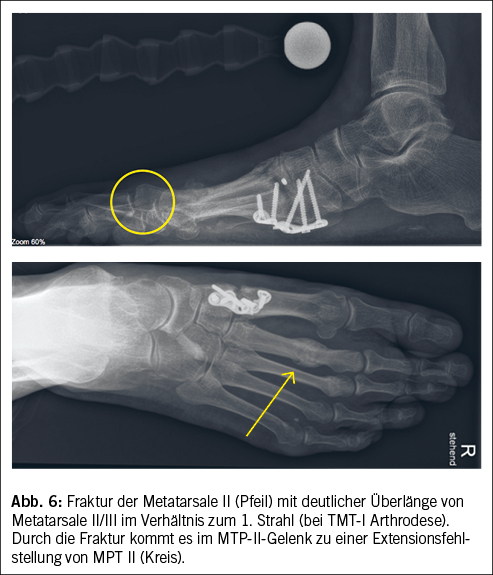

Durch Frakturen an den Metatarsalia kann es zu Fehlstellungen und ebenfalls nicht physiologischen Belastungen in den MTP-Gelenken kommen (Abb. 6).

Iatrogene Ursachen der Metatarsalgie sind bedingt durch chirurgische Voreingriffe, zum Beispiel einer Hallux-valgus-Korrektur mit Verkürzung des Metatarsale I (Abb. 6), Versteifung des Grosszehengrundgelenks, diverse Zeheneingriffe sowie wiederholte Steroidinfiltrationen. Steroide zeigen neben der gewünschten antiinflammatorischen Wirkung auch negative Effekte wie Schwächung der Sehnenstrukturen, Knorpelschädigungen sowie Ruptur der Gelenkkapsel mit daraus folgender Gelenkinstabilität (8).